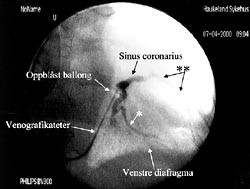

Etter punksjon av v. subclavia og innsetting av veneintroduser, innføres en lang ledesonde til høyre atrium under røntgengjennomlysning, oftest i flere plan. Over ledesonden innføres et spesiallaget introdusersystem med en 40 – 45 cm lang introduserhylse over en 54 cm lang dilatator til sinus coronarius. Etter at introduseren er plassert i stabil posisjon i sinus coronarius, innføres et 80 cm langt venografikateter med en lateksballong ved tuppen på kateteret til sinus coronarius. Denne ballongen kan blåses opp til en diameter på 10 mm og okkludere sinus coronarius helt eller delvis mens man injiserer kontrast og tar røntgenbilde av koronarvenene. Koronarveneanatomien har vist seg å variere fra pasient til pasient. Venogrammet gir et bilde av hvilke vener som er tilgjengelige for plassering av pacemakerledningen (fig 1). Man tilstreber å få spissen av pacemakerledningen plassert distalt i en lateral koronarvene. Til tross for spesielle vinklinger av ledningen er det ofte meget vanskelig å få plassert spissen på ledningen i ønsket posisjon. Kriteriene på en god posisjon av ledningen er at terskelen for stimulering av venstre ventrikkel ved 0,5 ms pulsvarighet er maksimum 3,0 V og at R-bølgen> 4,0 mV. Det må ikke forekomme stimulering av n. frenicus med diafragmastimulering ved høyeste spenning 7,5 V. Elektrogrammet avledes fra ledningen i koronarvenen og elektrogrammets konfigurasjon avgjør om ledningen er korrekt plassert over venstre ventrikkel.

Terskelen for stimulering må kontrolleres også etter at introduserhylsen er fjernet og ledningen er fiksert, fordi ledningen lett kan dras ut av posisjon pga. den kraftige medstrømmen som er i sinus coronarius når man skal fjerne den 45 cm lange innføringshylsen. Deretter innføres en standard bipolar pacemakerledning via introduser i v. cephalica til apeks av høyre ventrikkel. Dersom pasienten har sinusrytme, innføres også en standard bipolar atriepacemakerledning via ny introduser i v. cephalica til høyre atriumsaurikkel (fig 2). Etter at høyre ventrikkel-ledningen er plassert, avledes elektrogrammet fra høyre ventrikkel og epikardialt fra venstre ventrikkel via pacemakerelektroden i kornarvenen simultant både på EKG-skriver og med pacingsystemanalysator (Medtronic analyzer 8090TM). Med skriverhastighet 100 mm/s måler man den interventrikulære ledningstiden ut fra elektrogrammene fra høyre ventrikkel og fra venstre ventrikkel (fig 3). Det bør være lengst mulig spredning i tid mellom ventriklenes spontane aktiveringselektrogrammer for at man ved pacing skal få best mulig resynkronisering av høyre og venstre ventrikkel. Tersklene for stimulering, P-bølgeamplituden og R-bølgeamplituden måles i henholdsvis høyre aurikkel og høyre ventrikkel med pacingsystemanalysator. Til slutt kobles alle ledningene til pulsgeneratoren InSyncTM som plasseres i pacemakerlommen.